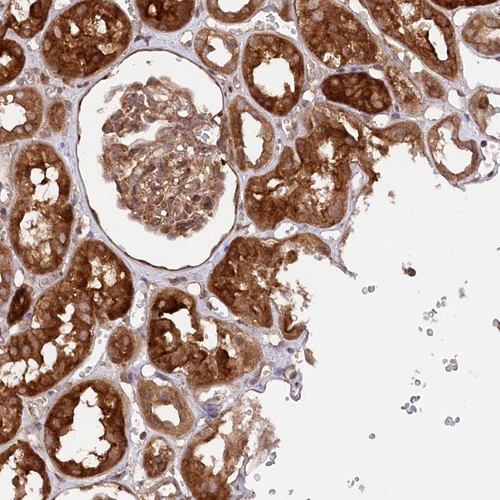

Immunohistochemical staining of human kidney shows strong cytoplasmic positivity in cells in tubules and cells in glomeruli.